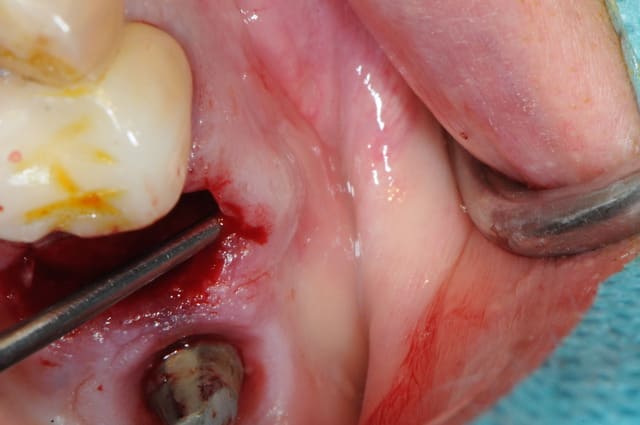

ton intervention, albert, me rappel un cas clinique que j'aimerai partager avec vous:

1-2-3 prémolaire foutu juste à proximité d'un implant, faut donc faire gaffe aux tissus environnant.

en plus je suis sure que la corticale vestibulaire est K.O elle aussi.

4-5: eh ben oui, elle est détruite! une simple curette insérée dans l'alvéole permet de visualiser l'importance de la perte osseuse vestibulaire.

que faire ??

1- curette en appuie sur la face vestibulaire montrant la destruction osseuse.